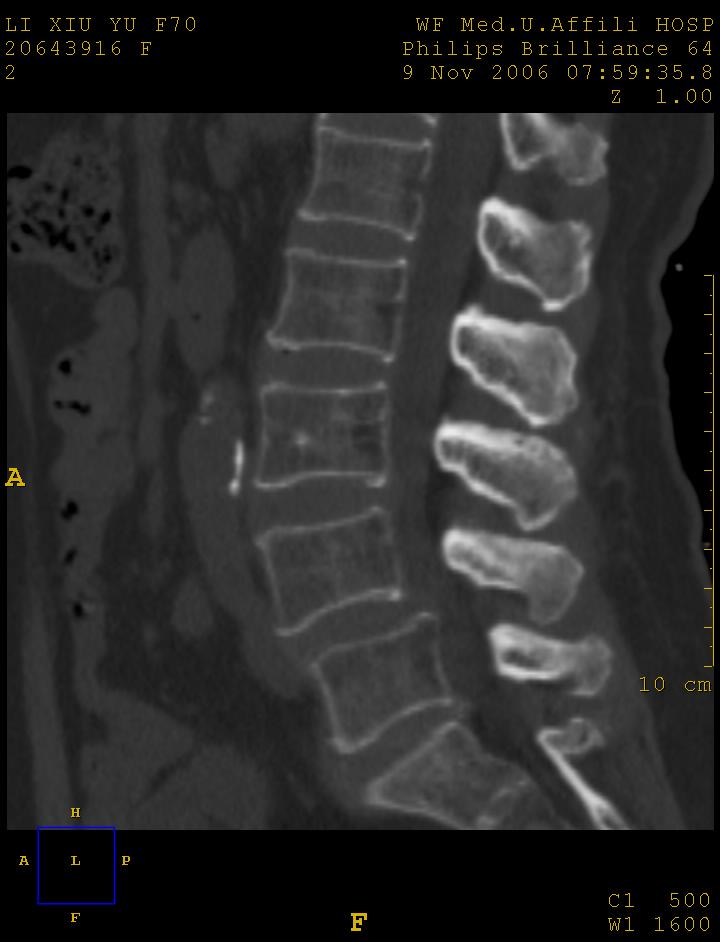

标题: CT5427:女,70岁,腰痛,清晰明了 [打印本页]

女,70岁,腰痛

l4以上向前滑脱

1腰椎骨质增生,2l4向前滑脱,3腰5-骶一椎间盘退变

l4椎体向前滑脱,椎弓裂

l3/4,l4/5,l5/s1椎间盘病变,l4以上向前ι度滑脱并椎小关节交锁、椎弓峡部断裂,椎小关节变性.

考虑:1、腰4假性前滑脱(1度,小关节退行性性骨关节病所致);

2、腰5--骶1椎间盘退行性变。

1、腰4椎体1度滑脱。2、腰椎及椎小关节退行性骨关节病。3、腰3-骶1椎间盘病变。

1:l4向前滑脱,l4-5小关节退性变。没有峡部裂。

1腰椎骨质增生,2l4向前滑脱(假性,矢状位椎弓峡部连续),3腰5-骶一椎间盘退变,4小关节面综合征

1 腰4椎弓崩裂,腰4椎体向前ι度滑脱并椎小关节交锁,腰4/5小关节明显增生硬化,间隙内可见真空征。

2 腰椎间盘不同程度膨出,腰4/5、腰5/骶1椎间盘突出,腰4/5椎间隙变窄,腰5/骶1间盘变性(间隙内可见真空征)。

3 诸椎体缘不同程度骨质增生,腰5、骶1后骨刺明显,腰5椎体后上缘可能有软骨结节(由于没有平扫,不易确定)。

诊断:腰椎退行性骨关节病。